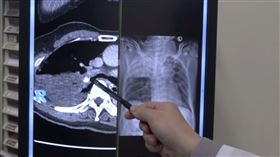

塵肺症結石鑿穿食道 醫示警:嚴重恐換肺

國內出現因為塵肺症讓氣管、食道被結石「鑿洞」的個案,...

咳嗽竟噴出石頭 男子食道被結石「鑿洞」

一名60多歲男性,從事石雕工作達20~30年,長期有...